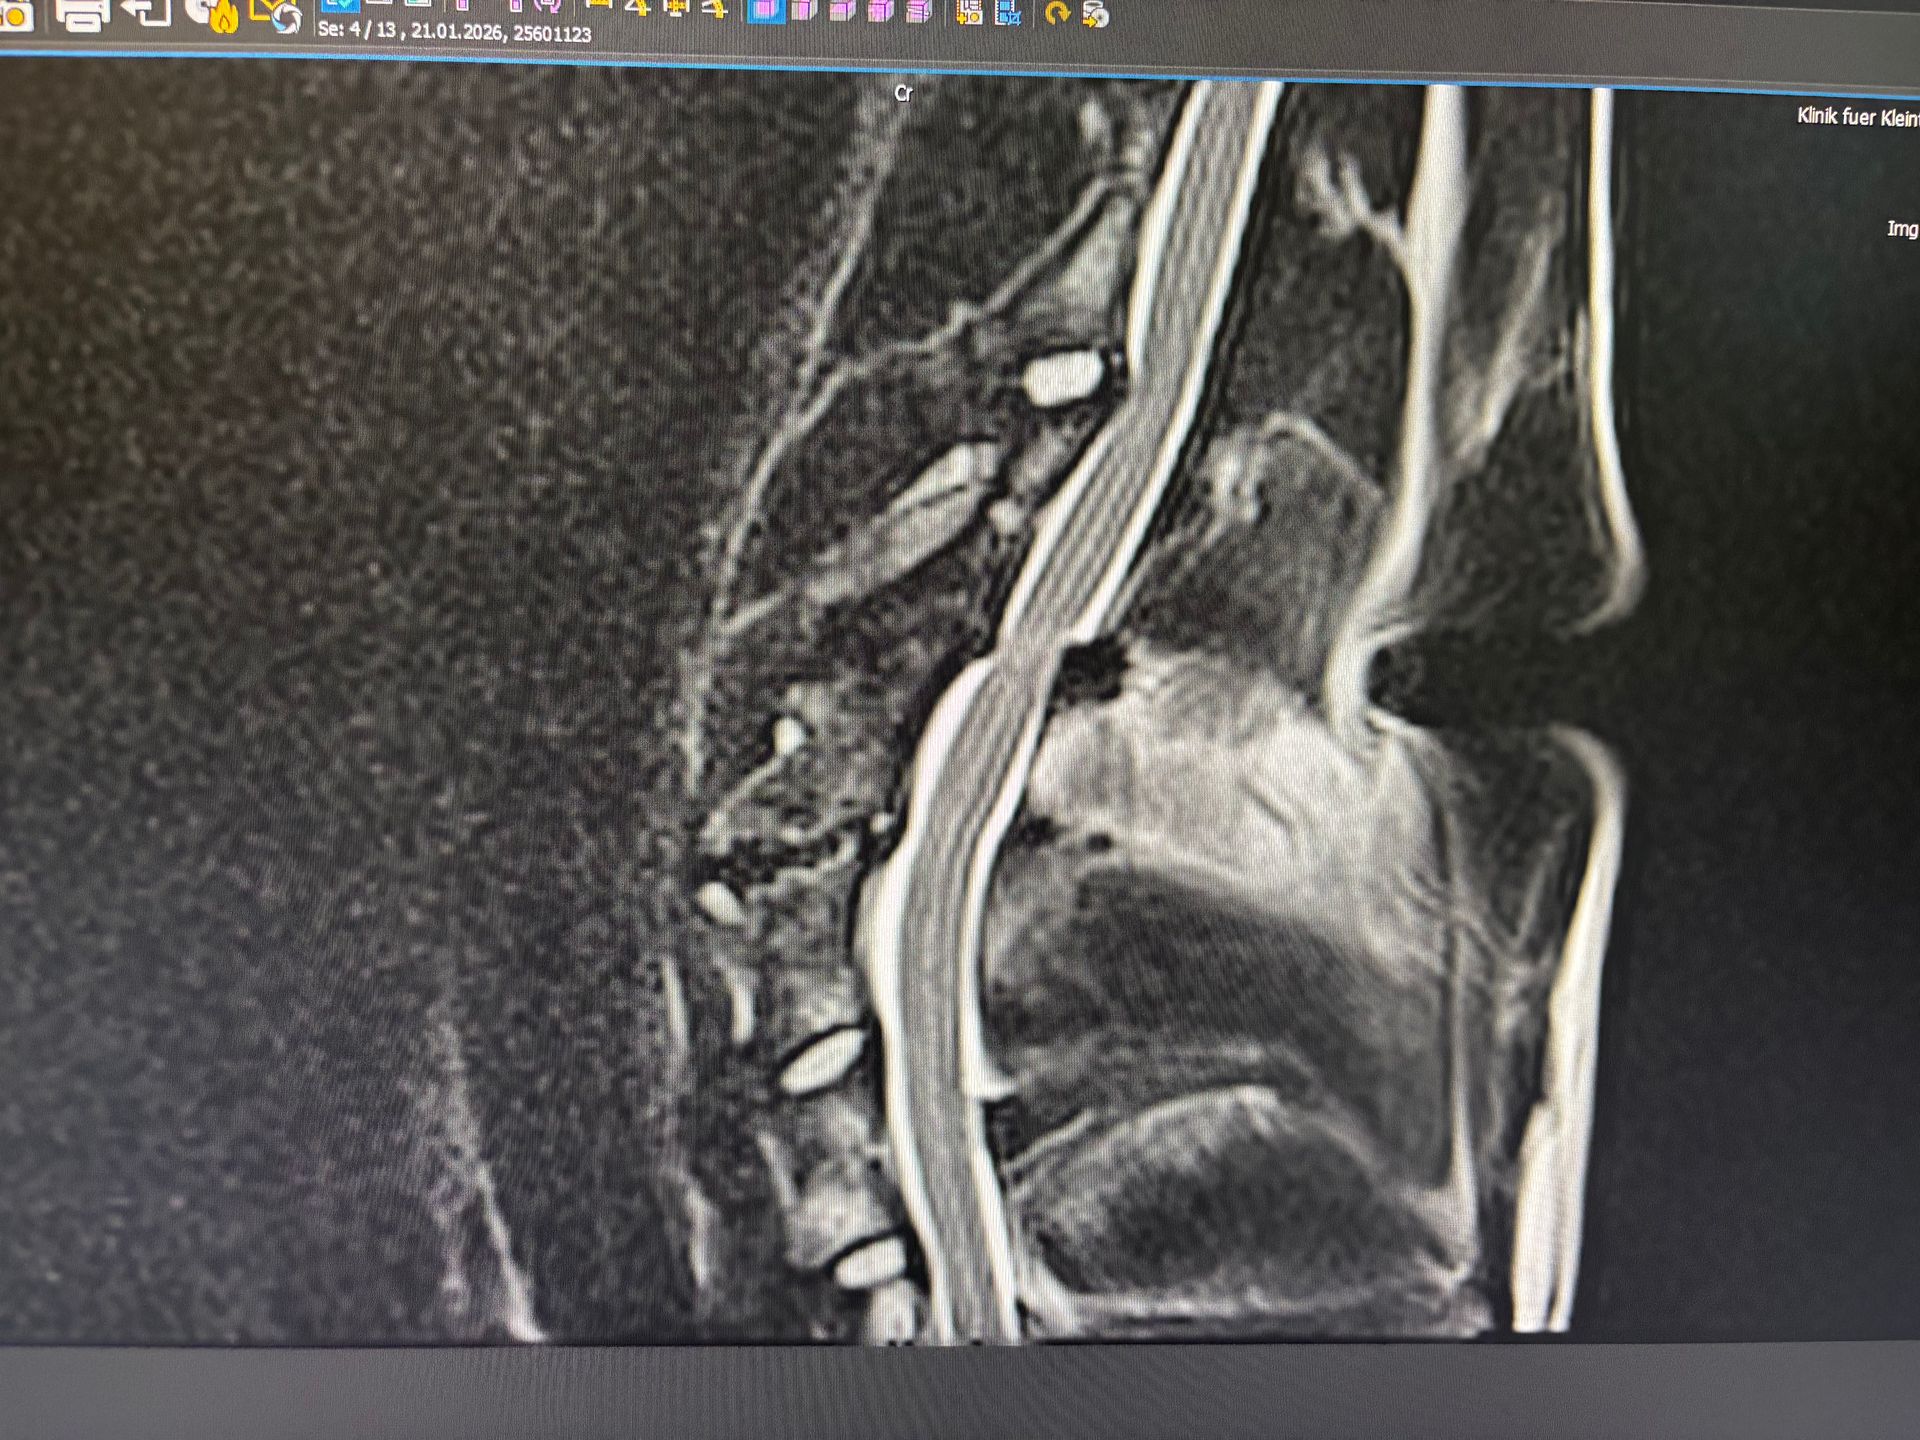

Die Diagnose lautet Diskospondylitis (nicht mehr akut) mit Bandscheibenveränderungen und Spondylosen.

Ein MRT, ein Abdomeschall und eine Liquor Punktion brachte dann die Ausprägung und Folgen zutage.

U.a. Zerstörung der vertebralen Endplatten an mehreren Wirbeln, Verengungen der Zwischenwirbelspalten und in einem Bereich ist die Bandscheibe derart verändert, dass man am Rückenmark schon erste Anzeichen einer Komprimierung sieht.

Was schlussendlich die Diskospondylitis ausgelöst hat und wann, können wir nicht mehr eruieren. Sie ist zumindest nicht mehr aktiv und daher auch nicht behandlungsbedürftig. Die Veränderungen an den Wirbeln und Bandscheiben sind aber nun leider da und auch nicht reversibel. Auch erste Arthrosen lassen sich bereits erkennen.

Was bedeutet das nun für Alma…? Sie braucht dauerhaft starke Schmerzmittel und Physiotherapie.

Und sie wird mit sehr großer Wahrscheinlichkeit irgendwann einen Bandscheibenvorfall in der HWS bekommen, der dann operiert werden muss.